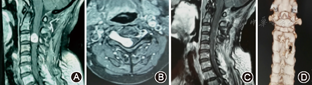

根据肿瘤位置采用后正中入路12例,其中内固定2例;颈前入路3例,内固定1例。(1)后正中入路:术前X线片定位病变节段,全麻后患者俯卧位,半椎板(9例)或全椎板(3例)入路,半椎板入路切除病侧半椎板,全椎板入路截取棘突椎板复合体,均保留棘上韧带和棘间韧带,显微镜下切开硬脊膜,瘤内分块切除内容物,体积缩小后分离肿瘤供瘤动脉及责任神经根,将肿瘤从脊髓上分离切除,先处理椎管内部分,后处理椎管外部分,肿瘤切除完毕后在椎间孔后以人工硬膜覆盖并用生物胶固定防止脑脊液漏。半椎板入路不予固定(图1),全椎板入路行棘突椎板复合体原位回植椎管成形术[5],彻底止血,逐层缝合,不留死腔。2例肿瘤侵犯椎弓根及椎体,予以病侧螺钉内固定以防脊柱失稳。(2)颈前入路:经胸锁乳突肌和颈内动脉鞘内侧钝性分离,避开颈总动脉和颈内静脉,显露椎旁肿瘤和扩大的椎间孔出口,瘤内减压后分离瘤壁与周围血管及神经的粘连,注意保护椎动脉,切除残余肿瘤。其中1例属肖氏分期Ⅳ期,椎体受侵犯严重,肿瘤显微镜下全切后予以椎体重建及固定融合术(图2)。

本组15例患者的肿瘤均显微镜下一期全切,且椎动脉均未受损(图3)。术后病理学诊断示:神经鞘瘤14例,神经节细胞瘤1例。术后无脑脊液漏及切口感染。术后Frankel分级显示,患者脊髓功能恢复D级4例,E级11例。随访1~24个月,平均13个月,无肿瘤复发及脊柱失稳。新发感觉麻木区域或原区域扩大者3例,10~12个月部分缓解。